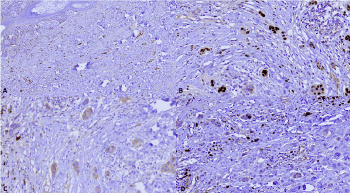

The patient underwent a mastectomy and sentinel lymph node dissection. Macroscopic examination of the breast identified nipple erythema and an 8 mm well-circumscribed nodule in the upper external quadrant. A detailed histologic examination of the fibrous zones was performed, in which an 8 mm fibroadenoma (previously biopsied specimen) was observed. Also, another 2 mm fibroadenoma was identified. Moreover, a radial scar and moderate ductal hyperplasia were found. The nipple histologic examination confirmed the incisional biopsy findings, an intraepidermal neoplasm characterized by cells with enlarged nuclei with pale cytoplasm arranged in a pagetoid pattern and directly beneath it, there was invasive cancer into the dermis which formed little glands and nests (Figure 4). No carcinoma in situ or another focus of infiltrating carcinoma was observed. The invasive neoplasm was categorized as an infiltrating carcinoma, not special type grade 2 with a 3 mm depth invasion. Both estrogen and progesterone receptors were positive in 90% of the cells, Her2/Neu negative (1+), and the Ki67 index was 10%. Surgical margins and the sentinel lymph node were negatives (Figure 5).

Figure 4. Mastectomy, nipple section. A. Acantholytic pattern of Paget disease, B. Direct invasion into the subjacent dermis in forms of glands and nests

Figure 5. Immunohistochemistry profile A. Estrogen receptors positive in 90% of the cells. B. Progesterone receptor-positive in 90% of the cells. C. Her2/Neu was negative (1+). D. Ki-67 was positive in 10% of the cells